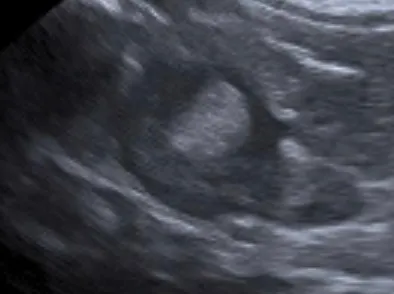

➡️腹腔超音波區別腎上腺的型態:超音波可以分辨腎上腺的對稱性,通常PDH兩邊的腎上腺是對稱的。如果是腎上腺腫瘤,會失去內部正常的結構,另一側的腎上腺也會比較小(腎上腺高度會小於0.4-0.5cm),

通常腎上腺腫瘤是單側的,但也有可能出現雙側。腎上腺腫瘤跟巨型節結性增生 (micronodular hyperplasia) 難用影像區分,但一般腎上腺高度如果大於四公分則通常是惡性的。腎上腺腫瘤會侵入後腔靜脈,轉移到腹腔其他器官或是胸腔。

正常的腎上腺型態

腫大的腎上腺型態